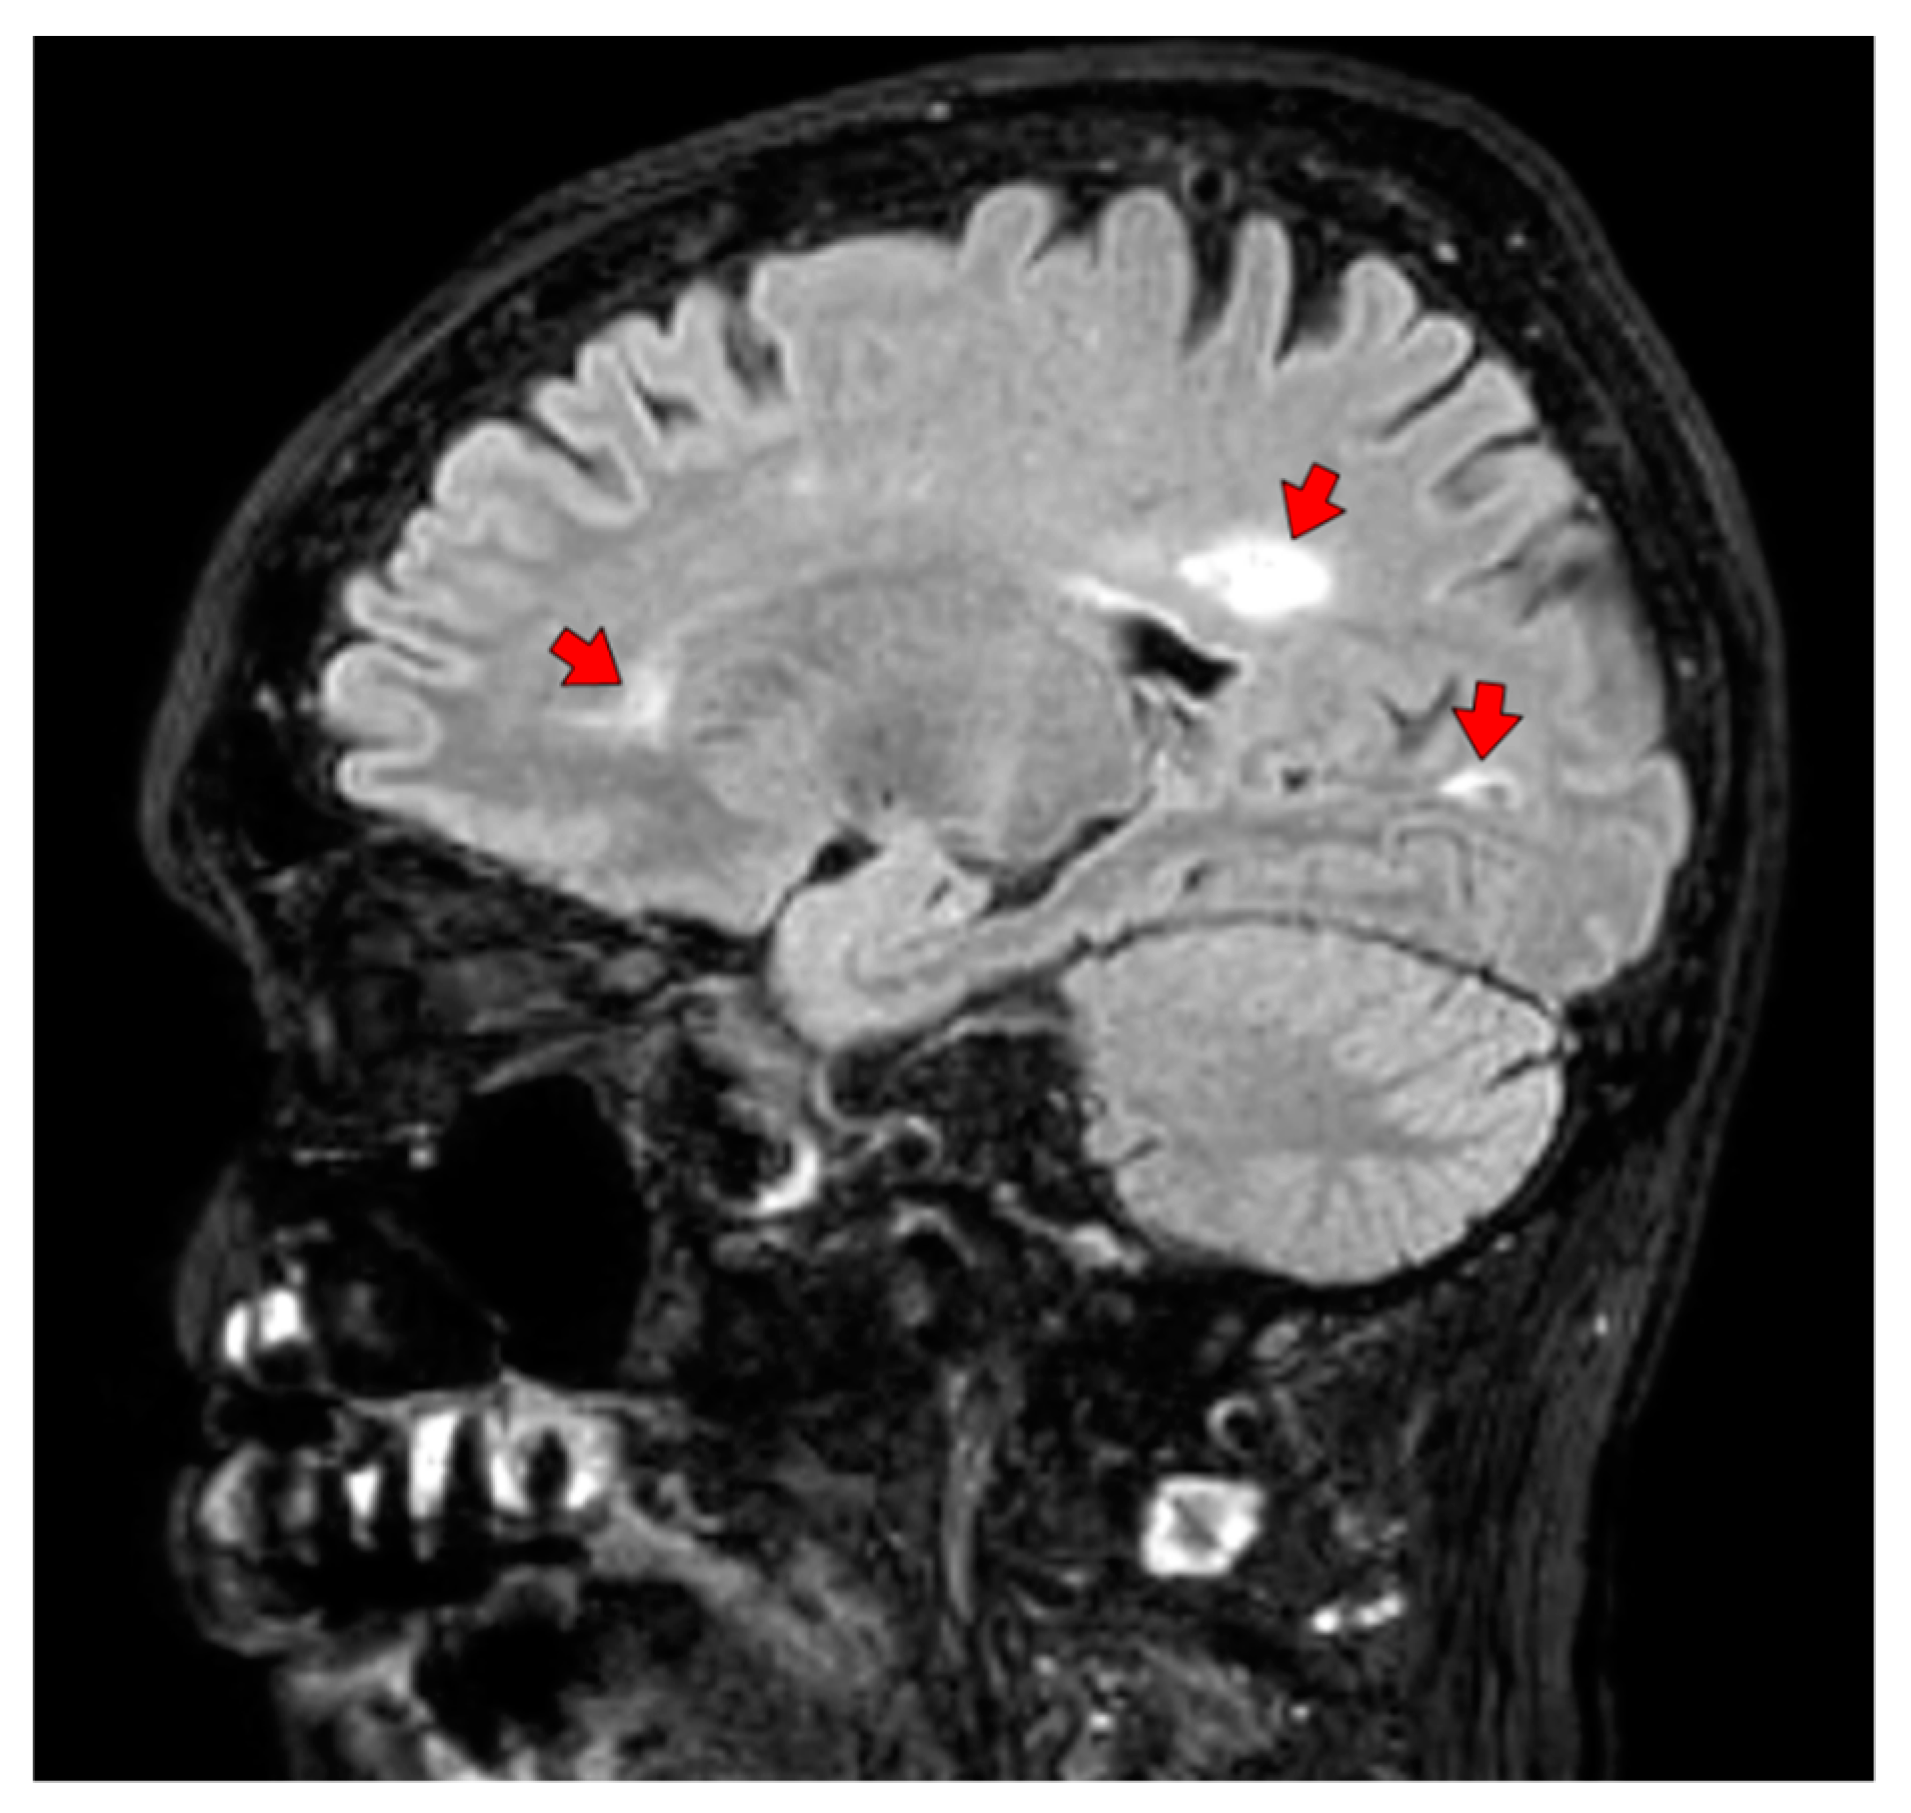

| Brain MR Findings | |||

| Brain Involvement (any location) | 52 (91%) | 16 (53%) | <0.001 * |

| Number of Subcortical White Matter Lesions: | |||

| 0 | 10 (18%) | 16 (53%) | |

| 1 | 30 (53%) | 13 (43%) | 0.001 * |

| 2 | 11 (19%) | 1 (3%) | |

| 3 | 6 (11%) | 0 (0%) | |

| Number of Deep White Matter Lesions: | |||

| 0 | 25 (44%) | 24 (80%) | |

| 1 | 21 (37%) | 4 (13%) | 0.014 * |

| 2 | 10 (18%) | 2 (7%) | |

| 3 | 1 (2%) | 0 (0%) | |